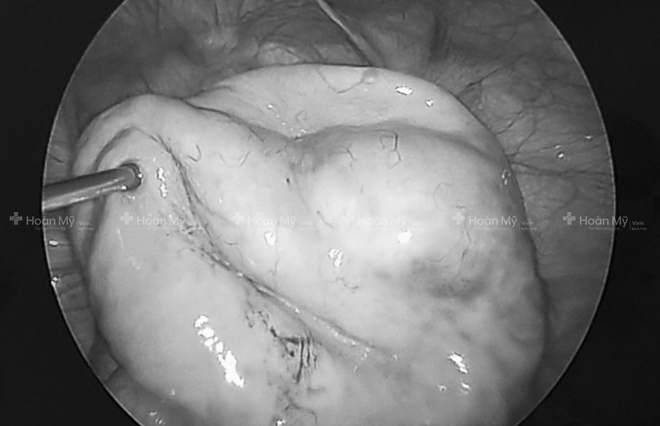

Sau khi hội chẩn, các bác sĩ đã tiến hành phẫu thuật nội soi bóc tách khối u ra ngoài. Ca phẫu thuật kéo dài 90 phút đã lấy hết toàn bộ khối u cùng 2,5 lít dịch ra ngoài cho bệnh nhân H.

Cô gái 21 tuổi tưởng đang mang thai, hóa ra mang khối u khủng - Ảnh 2.

Các bác sỹ tiến hành phẫu thuật nội soi lấy khối u ra cho bệnh nhân.